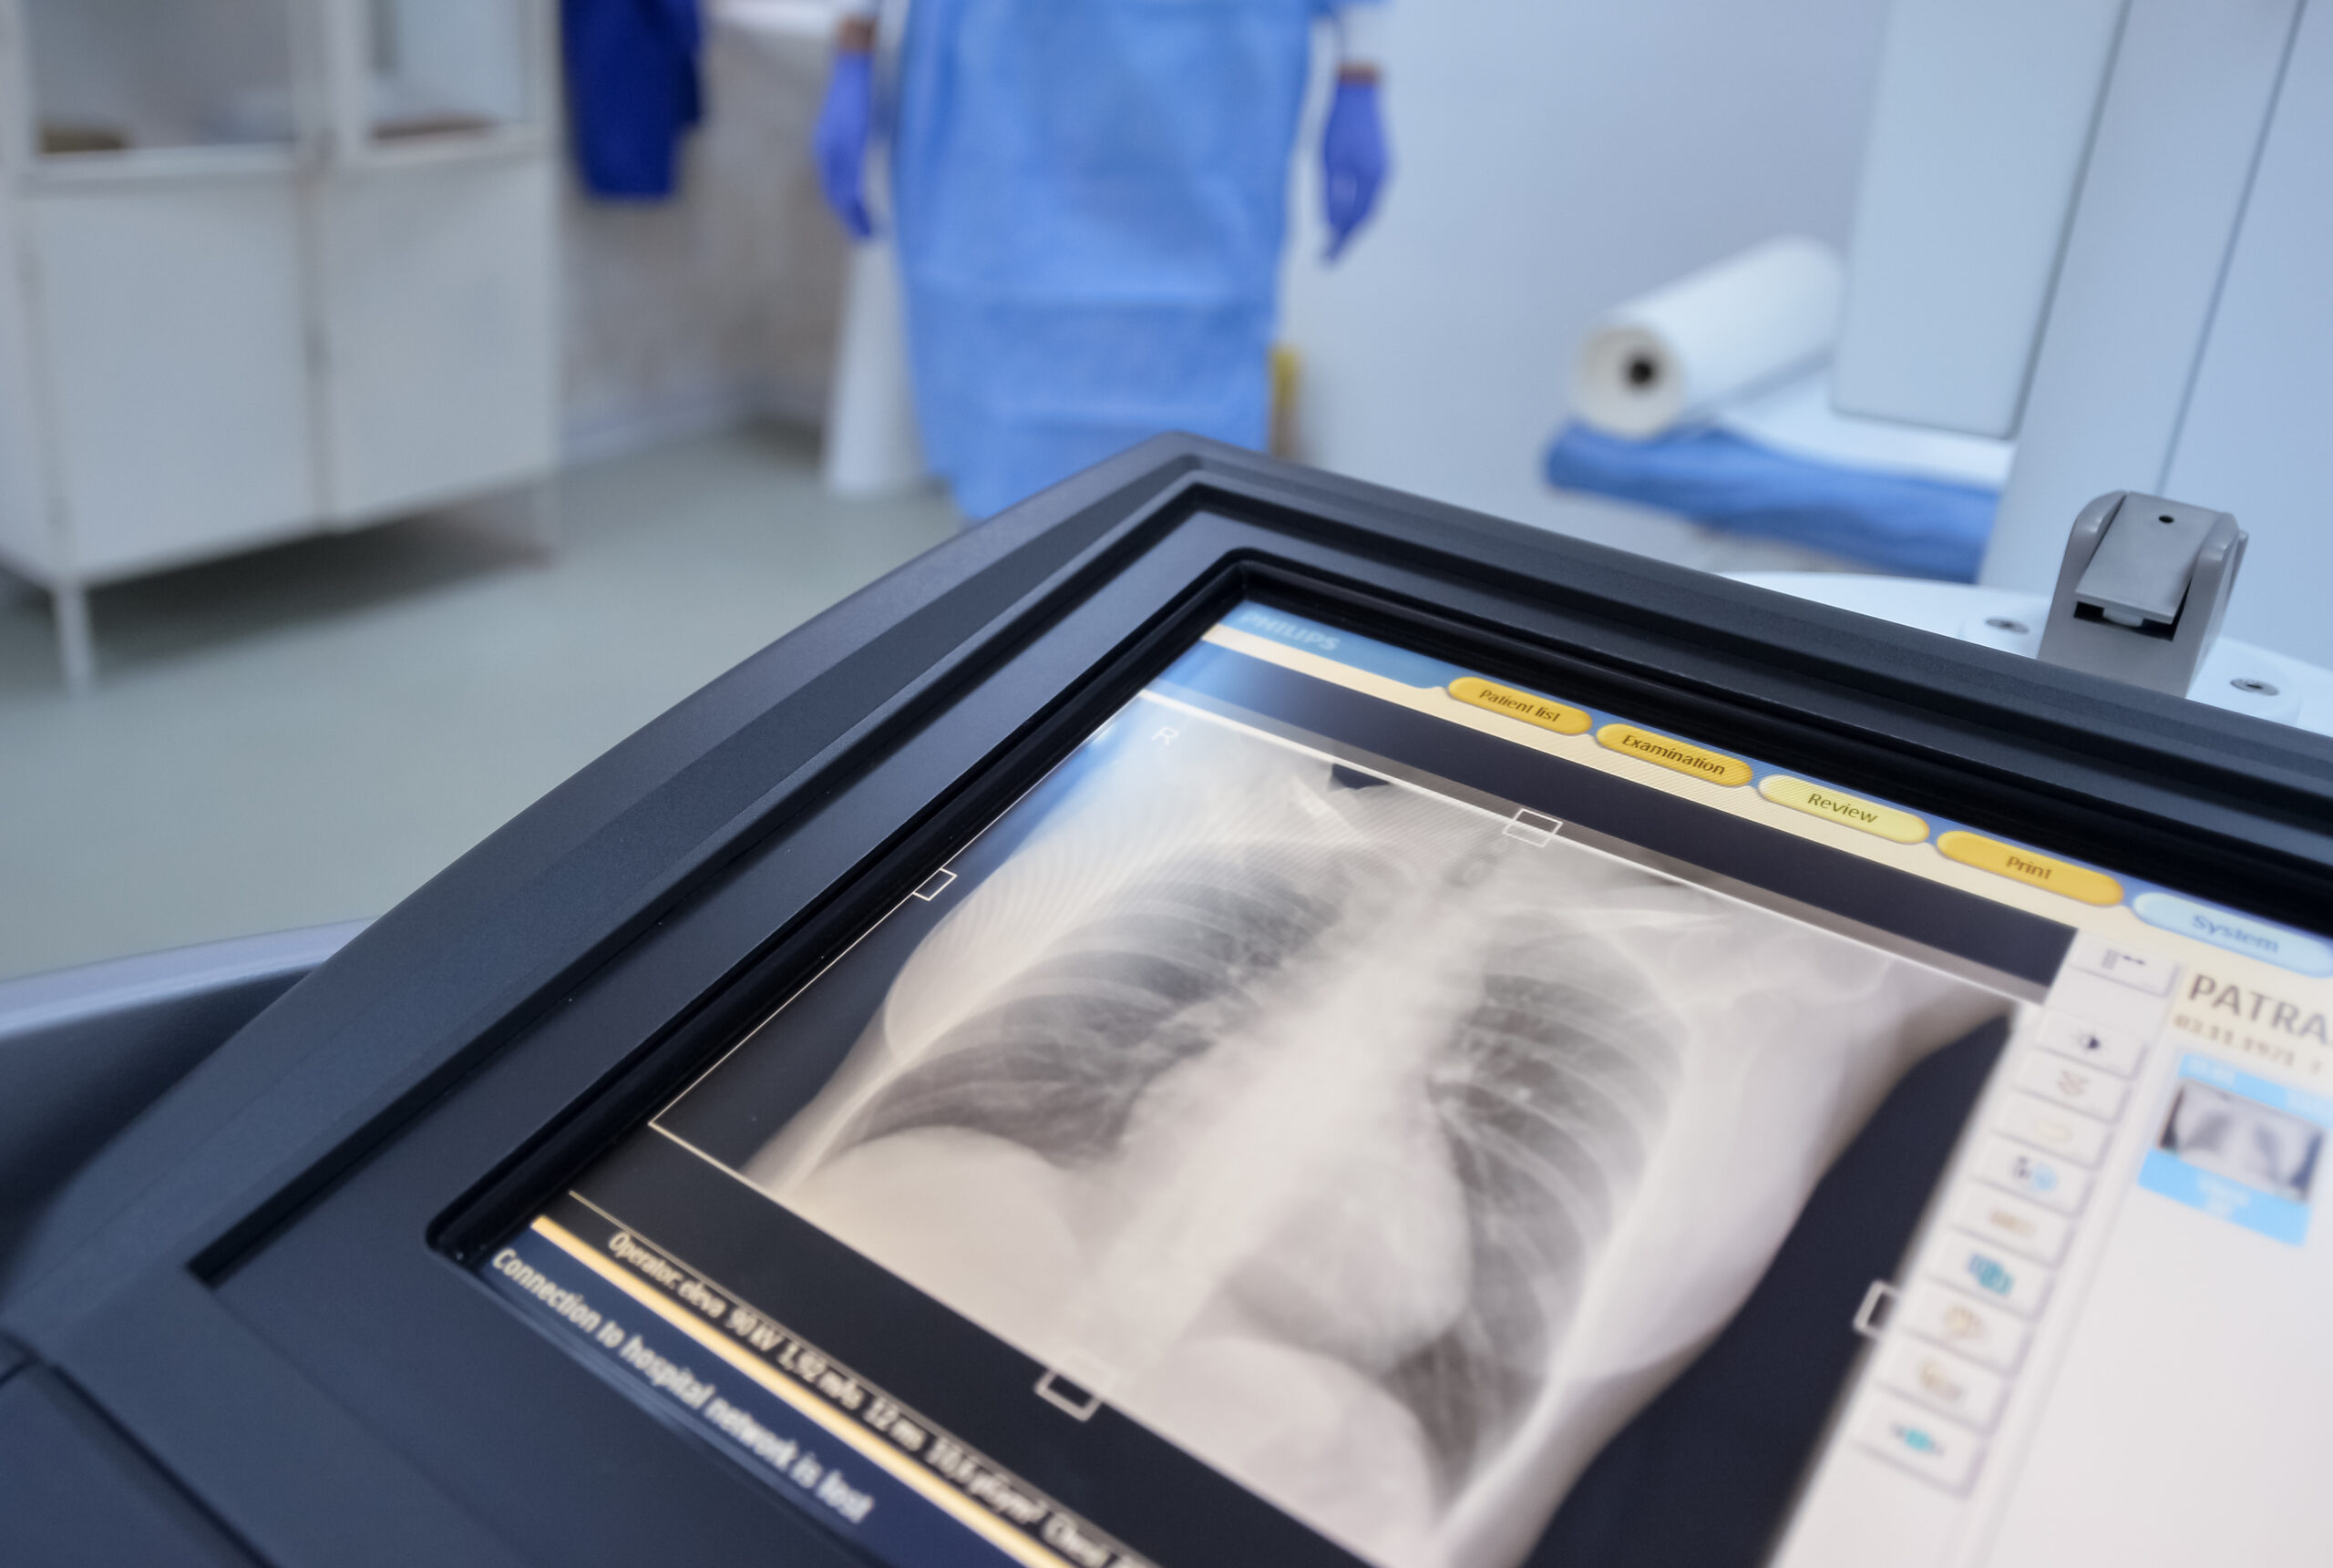

O radiografie banală a arătat prezența unui ac de cusut în plămânul stâng al pacientei, care ar fi rămas în organism, timp de 30 de ani.

„Radiografia care m-a lăsat fără cuvinte după 20 de ani de experiență. În radiologie vezi de toate. După 20 de ani, crezi că nimic nu te mai poate surprinde. Și totuși. O pacientă de ~55 de ani vine pentru o radiografie pulmonară de rutină. Control periodic, nimic special. Pun radiografia pe ecran. Și…